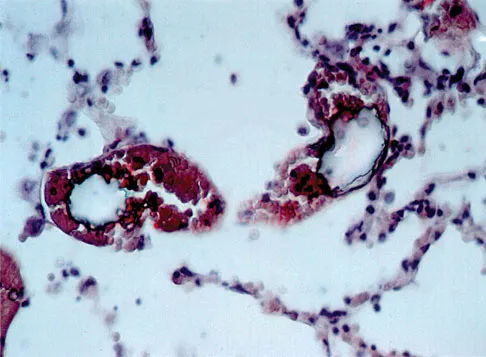

Figure 49 shows a histologic section of the lung in a patient who died during total hip arthroplasty. What unexpected finding is seen in the pulmonary capillaries?

Explanation